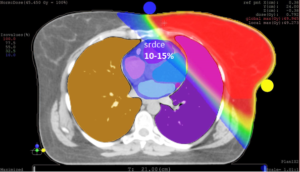

Obrázek č. 1: Příklad fotonového plánu vytvořeného pomocí techniky 3D CRT a protonového plánu vytvořeného pomocí techniky IMPT. Zde je zřejmé, že protonový plán je mnohem šetřivější než fotonový, zejména z pohledu maximální dávky na srdce a rovněž dávky na plíce. Určitou dávku obdrží i kontralaterální prs, což přináší určité riziko sekundárních malignit.

Fontanila a kol.1) publikovali v roce 2012, že může být pokrytí cílového objemu u fotonové radioterapii obtížné při nutnosti ozářit vnitřní mamární uzliny. Autoři retrospektivně analyzovali pokrytí hrudní stěny, uzlinových oblastí (axilární I, II, III, nadklíčkové a vnitřní mamární uzliny) pro reálně provedené plány. Všechny plány byly konturovány dle RTOG doporučení. Požadovanou dávkou bylo pokryto 74% objemu u hrudní stěny, 80% objemu u vnitřních mamárních uzlin, porytí axilárních a nadklíčkových uzlin bylo velmi dobré. Přes tyto kompromisy byl objem srdce ozářený více než 10 Gy u levostranných tumorů prsu 11% a u pravostranných tumorů 6%. Objem plic ozářený dávkou 20 Gy (V20) ipsilaterální plíce představoval u levostranných karcinomů prsu 28 % a u pravostranných karcinomů prsu až 34%. Výsledky prokazují poměrně vysokou radiační zátěž. Při použití protonové radioterapie nutnost kompromisů a zbytečná radiační zátěž zdravých tkání odpadá.